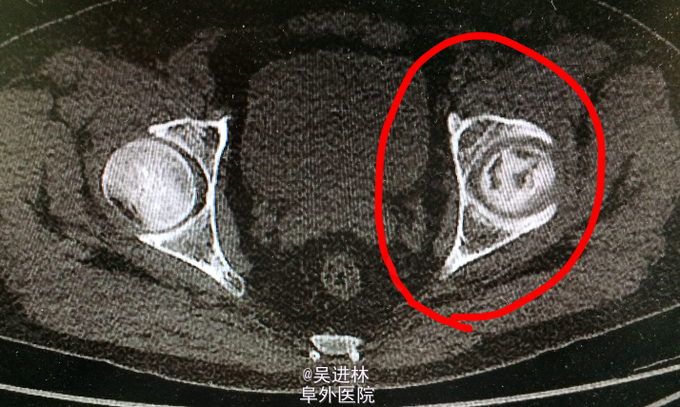

患者老年男性,主因“左髋部疼痛不适2年余”入院;查体:左侧腹股沟压痛+;活动度受限;4字试验+,托马斯征+;辅助检查:CT示左侧髋臼骨多发骨质破坏,累及周围软组织;全身骨显像示左髋臼窝核素浓聚灶;MIR描述如图。T-spot阳性!现在对于诊断基本持两种意见:因为患者病灶累及软组织,MRI上髂腰肌可见高信号,而且T-spot阳性,考虑TB。另外一种观点认为:病人除了T-spot并无其他TB征象,而且如果是TB的话,现在早就应该形成冷脓肿和窦道了,再者从MRI上来看,病灶呈膨胀性生长,边界清楚,所以考虑骨肿瘤可能性。what do you think?